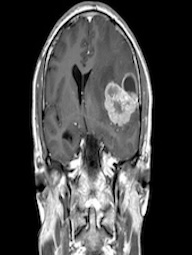

Brain Tumor MRI dataset:

The Brain Tumor MRI Images dataset is a publicly available dataset on Kaggle555https://www.kaggle.com/datasets/sartajbhuvaji/brain-tumor-classification-mri/data. It contains MRI images of human brains divided into four categories: No Tumor, Pituitary Tumor, Benign Tumor, and Malignant Tumor. For our study, we selected three categories: No Tumor (NT), Benign Tumor (BT), and Malignant Tumor (MT). From each category, we chose three MRI images representing different parts of the brain that best illustrate the characteristics of each class. The categories included in this study are described as follows:

The No Tumor (NT) category contains MRI images of healthy brains with no abnormal growths or masses. In these images, the brain tissue appears normal, and there are no signs of tumors or unusual structures. These images serve as a baseline, allowing for effective comparison and detection of abnormalities in other MRI scans.

Refer to caption

(a) NT1

(b) NT2

(c) NT3

(d) BT1

(e) BT2

(f) BT3

(g) MT1

(h) MT2

(i) MT3

Figure 5. Axial and Coronal MRI Images of Brains Representing Different Tumor Categories

The Benign Tumor (BT) category includes MRI images showing non-cancerous tumors in the brain. Benign tumors grow slowly and do not spread to other parts of the brain or body. While generally less dangerous than malignant tumors, they can still cause symptoms if they press on surrounding brain tissue. Accurate identification of benign tumors is important for planning appropriate treatment, which may involve monitoring, minor surgery, or other non-aggressive interventions.

The Malignant Tumor (MT) category consists of MRI images showing cancerous tumors. These tumors are aggressive, can grow rapidly, and may spread to other parts of the brain or body. Malignant tumors require immediate and intensive treatment, such as surgery, chemotherapy, or radiotherapy. Differentiating malignant tumors from benign tumors is crucial, as it directly impacts the treatment strategy and can significantly affect patient outcomes.

Differentiating these categories is essential for early detection, accurate diagnosis, and effective treatment planning. By distinguishing between healthy brains, benign tumors, and malignant tumors, medical professionals can identify abnormalities more reliably, reduce misdiagnoses, and streamline medical care. In this study, we apply our divergence measure to differentiate between the selected MRI images, as illustrated in Figure 5. In Figure 5, the first row shows MRI images from NT patients, the second row shows images from BT patients, and the third row shows images from MT patients.

Using the divergence measure, we calculated estimates for each pair of MRI images and compared the three categories. For calculation, each grayscale image is represented by its pixel intensity values (scaled to [0,1]). These values are flattened into a one dimensional vector and used as the sample data for subsequent analysis. For any two images, denoted data1 and data2, we then computed an empirical based divergence estimate. The resulting values are presented in Tables 4, 5, and 6. A higher value of the divergence estimate indicates a greater likelihood of a tumor. These results demonstrate that the divergence measure can serve as an effective tool for detecting tumors in medical image data.

While our study demonstrates the effectiveness of the divergence measure in differentiating brain MRI images across tumor categories, the results could be further strengthened with longitudinal data, where MRI scans of the same individuals are available at different stages of tumor progression, captured with consistent size and image quality. The current dataset, being cross-sectional, limits the ability to draw more definitive conclusions regarding tumor evolution. Incorporating longitudinal data in future studies would provide deeper insights and allow for more robust validation of the divergence measure in tracking disease progression.